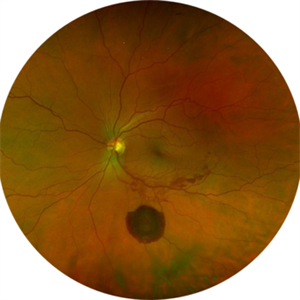

New Choroidal Melanoma

New Choroidal Melanoma

Jul 16 2025 by Virginia Gebhart

78 year old male with a partially amelanotic dome-shaped lesion with RPE changes, hard exudates, overlying intraretinal fluid and minimal SRF temporally. Exam and ultrasound findings consistent with choroidal melanoma. Pt will be scheduled for brachytherapy pending CT scan results.

Photographer: Virginia Gebhart, Retina Consultants of Carolina

Imaging device: Optos California

Condition/keywords: amelanotic melanoma, choroidal melanoma